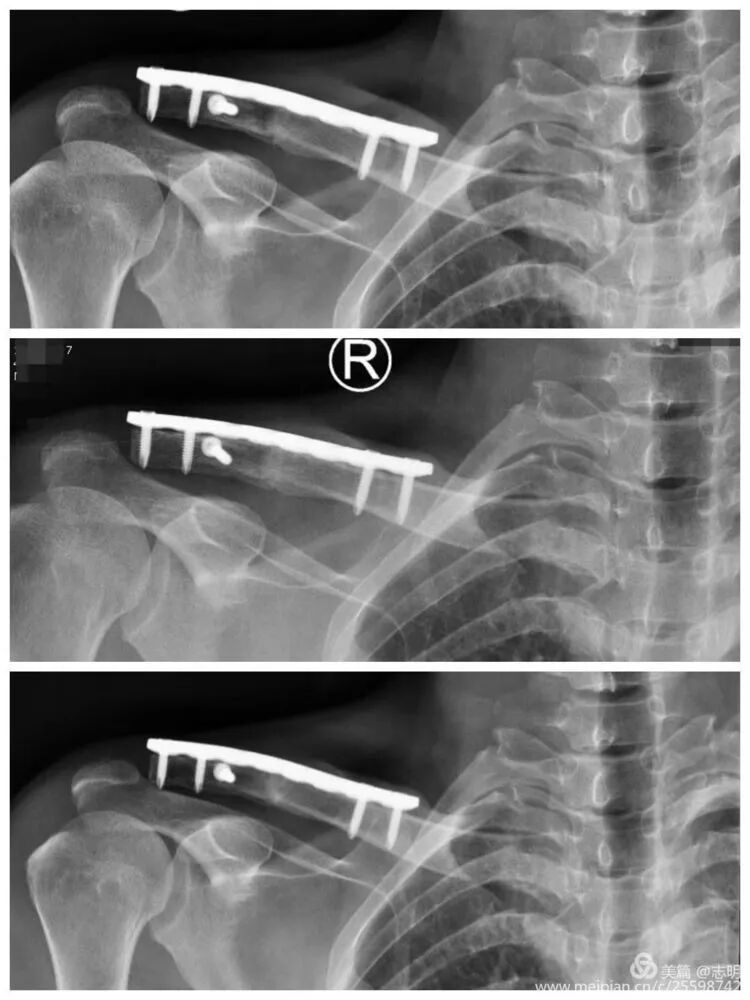

- Final Assessment: Once all screws are inserted, perform a final fluoroscopic assessment to confirm satisfactory fracture reduction, stable plate position, and appropriate screw lengths. Remove any temporary K-wires.

(Post-fixation X-ray).(Healed fracture X-ray).(Another post-fixation X-ray).

- Final Intraoperative Assessment: Once all screws are securely inserted, perform a comprehensive final fluoroscopic assessment. Verify satisfactory fracture reduction, confirm stable and flush plate position, and ensure appropriate screw lengths and trajectories. Any temporary K-wires are then removed.

(Post-fixation X-ray showing the plate and screws in place).(Another post-fixation X-ray).